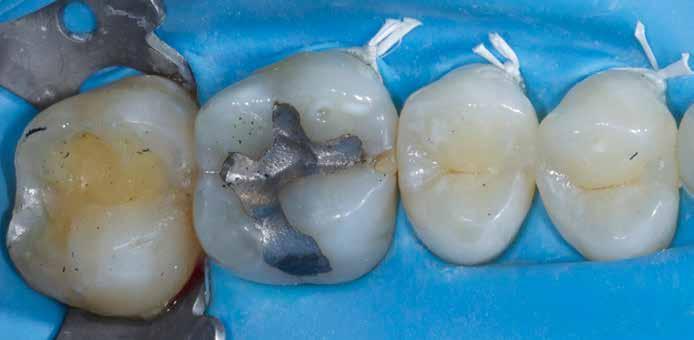

Egy 31 éves férfi páciens jelentkezett a jobb felső első molárisából kiinduló, reverzíbilis pulpitisre utaló tünetekkel. A klinikai vizsgálat során meglévő okkluzo-palatinális ezüsta-

malgám restauráció volt észlelhető, valamint szekunder caries mesiálian, a marginális gerinc kavitációjával együtt (10. ábra). A mesio-bukkális csücsök csúcsán kopási fazetta volt látható; a fog egyébként klinikailag és radiológiailag épnek bizonyult. A tájékoztatáson alapuló beleegyezést követően a kezelési terv II. osztályú, háromfelszínű direkt kompozit restauráció volt.

A szerző helyi érzéstelenítés után a fogat latexmentes kofferdámmal izolálta; a gumit befordította, és közben fogselyem segítségével interproximálisan visszahúzta (11. ábra)

Nagyítás alatt (operációs mikroszkóp) a régi restaurációt körte alakú gyémántfúróval távolította el, 1,5-es sebességfokozatú elektromos kézidarabbal kb. 45 000/ perc fordulatszámon vízhűtés mellett, így a mesiális oldalon feltárta a szuvasodást. A szerző az elektromos kézidarabot részesíti előnyben a nagy nyomaték és a kisebb, alacsonyabb sebességnél előforduló torpanási hajlam miatt. A szomszédos premoláris fogat ék (Triodent) segítségével védte az iatrogén sérülésektől (12. ábra). A szomszédos fog iatrogén sérülése jól dokumentált komplikációja a II. osztályú üreg dobozpreparációjának [18].

A cariest lépésről-lépésre távolította el, caries detektáló festék és a Peripheral-Seal koncepció [15] alkalmazásával, amely lehetővé teszi a magas kötőerejű, cariesmentes zománc- és dentinzóna kialakítását a kavitás peremén, miközben a mélyebben lévő, caries által érintett dentin megmarad remineralizáció céljából [16]. A preparáció szélét alumínium-oxid abrázióval kezelte a biofilm és az aprizmatikus zománc eltávolításának céljából, ezzel javítva a kötőerőt [17]; majd karbidfúrókkal elsimította, hogy eltávolítsa a mikroszkopikus szinten törött zománcprizmákat, így csökkentve a „Enamel Peel”-ből eredő fehér vonalak kialakulásának kockázatát (13. ábra) [18].

A fogat 37%-os foszforsavval kondícionálta, majd egy 4. generációs dentin bondot (Optibond FL, Kerr) alkalmazott. A II. osztályú dobozt először centripetálisan zárta [19], folyékony és melegített kompozit kombinációjával, szekciós matrica segítségével.

A dentint hiperkróm, közepes opacitású pasztakompozittal modellezte, amely optikai tulajdonságaiban utánozza a természetes dentint (14. ábra). A barázdarendszerbe okker árnyalatú színezőanyagot vitt fel a restauráció színintenzitásának fokozása érdekében (15. ábra).

Ezután közepes transzlucenciájú, zománcszínű kompozitot helyezett a kavitásba, az okkluzális iránytű technika alkalmazásával. Külsőleg sötétbarna színezést vitt fel a barázdák elszíneződésének imitálására (16. ábra).

A restauráció polírozását korongok és szilikonpolírozók kombinációjával végezte, majd az okklúzió ellenőrzését követően a pácienst a rendelőből otthonába bocsátották. Megjegyzendő, hogy a finírozást követően az eredeti okkluzális anatómia csak minimális mértékben módosult (17. ábra).